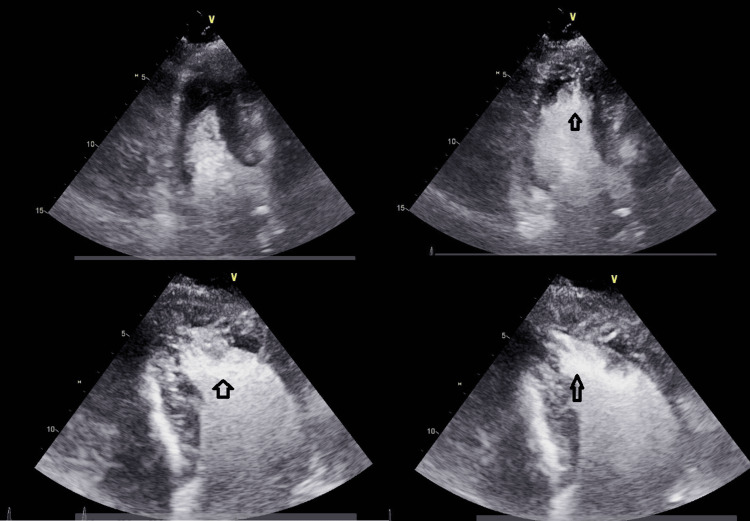

A transthoracic echocardiogram revealed hyperdynamic LV function with an ejection fraction (EF) greater than 70%, grade II pseudo normal filling dynamics, and mild to moderate concentric left ventricular hypertrophy (LVH) with asymmetric thickening of the apical segments consistent with Yamaguchi syndrome (Figure 2).

Figure 2. A transthoracic echocardiogram revealed mild to moderate concentric left ventricular hypertrophy with asymmetric thickening of the apical segment (black arrows).